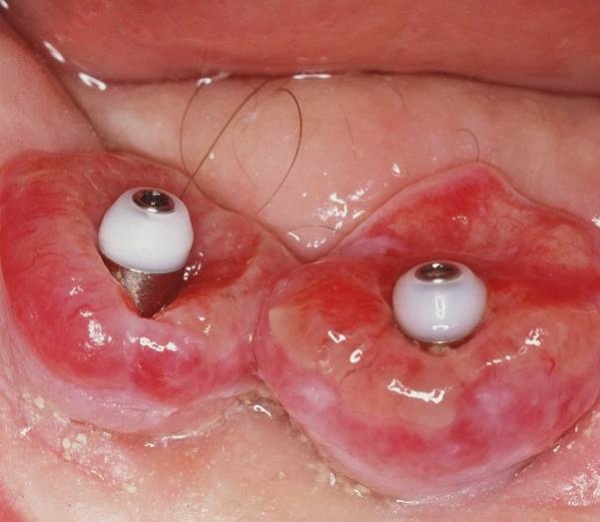

Aufgrund der fortgeschrittenen parodontalen Vorerkrankung musste mit der Planung und der Herstellung des definitiven Zahnersatzes lange gewartet werden. Zunächst wurden im Mai 2001 die erneuerungsbedürftigen Kronen der prognostisch als günstig beurteilten Zähne 11 und 21 erneuert. Im April 2002 wurde die Versorgung der Schaltlücke in regio 36 mit der Einbringung eines dentalen Implantats in regio 36 begonnen, die mit der Herstellung der implantatgetragenen Krone im November 2002 abgeschlossen wurde (s. Abb. 15). Das Langzeitprovisorium 23 auf 28 wurde im Oktober 2004 durch eine definitive Brücke von 23 auf 28 ausgetauscht.

Mit der Transplantation eines freien Schleimhauttransplantats im Januar 2001 konnte die aktive parodontologische Therapie abgeschlossen werden, der Patient wurde zur Unterstützenden Parodontitistherapie in das Recallsystem der FU VIIa aufgenommen. Der Patient stellte sich dabei halbjährlich zur Durchführung von professionellen Zahnreinigungen vor, die durch die bereits beschriebenen Elemente der Erhaltungstherapie ergänzt wurden. Ein wichtiges Element der Erhaltungstherapie ist die regelmäßige parodontale Diagnostik mit der Erstellung eines Parodontalstatus, um gegebenenfalls Rezidive frühzeitig erkennen und behandeln zu können. Im Jahre 2006 kam es an einzelnen Zähnen zu Rezidiven, es konnten Sondiertiefen von bis zu 7mm sondiert werden. Es wurde daher ein Scaling/Rootplaning der rezidivierenden Taschen durchgeführt, an einzelnen Zähnen erfolgten im Jahre 2008 zudem weiterführende parodontalchirurgische Maßnahmen im Sinne von Lappenoperationen (s. Abb. 16). Im Rahmen der unterstützenden Parodontitistherapie erfolgte neben den schon erwähnten halbjährlichen professionellen Zahnreinigungen im November 2012 eine erneute subgingivale Instrumentierung an 21, 24, 28, 41, 46. Die letzte Vorstellung des Patienten erfolgte im April 2015 (s. Abb. 17, 18, 19). Dabei stellte sich die marginale Gingiva entzündungsfrei dar, die approximalen Sondiertiefen betrugen durchschnittlich zwei bis drei Millimeter, geringgradig erhöhte Sondiertiefen verbleiben an 21, 28, 36, 47. Die häusliche Mundhygiene des Patienten stellte sich wie schon über den gesamten Beobachtungszeitraum mit einem API von 30 % als gut dar. Die periimplantären Gewebe zeigten sich bei der Vorstellung im April 2015 unauffällig.